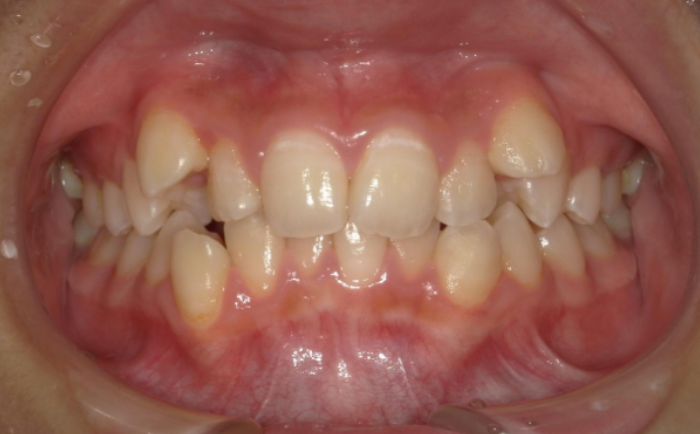

ガタガタが強く、歯の重なりが大きいケース

「前歯が大きくねじれている」「歯と歯が重なっていて、ほとんど隙間がない」といった、強いデコボコがあるケースです。 この場合、前歯だけを少し動かすだけではきれいに収まらず、奥歯を含めて歯列全体を広げたり、場合によっては抜歯でスペースを作ったりする必要が出てきます。無理に部分矯正だけでまとめようとすると、仕上がりが中途半端になったり、後戻りしやすくなったりするため、最初から全体矯正を前提に考えたほうが安心です。